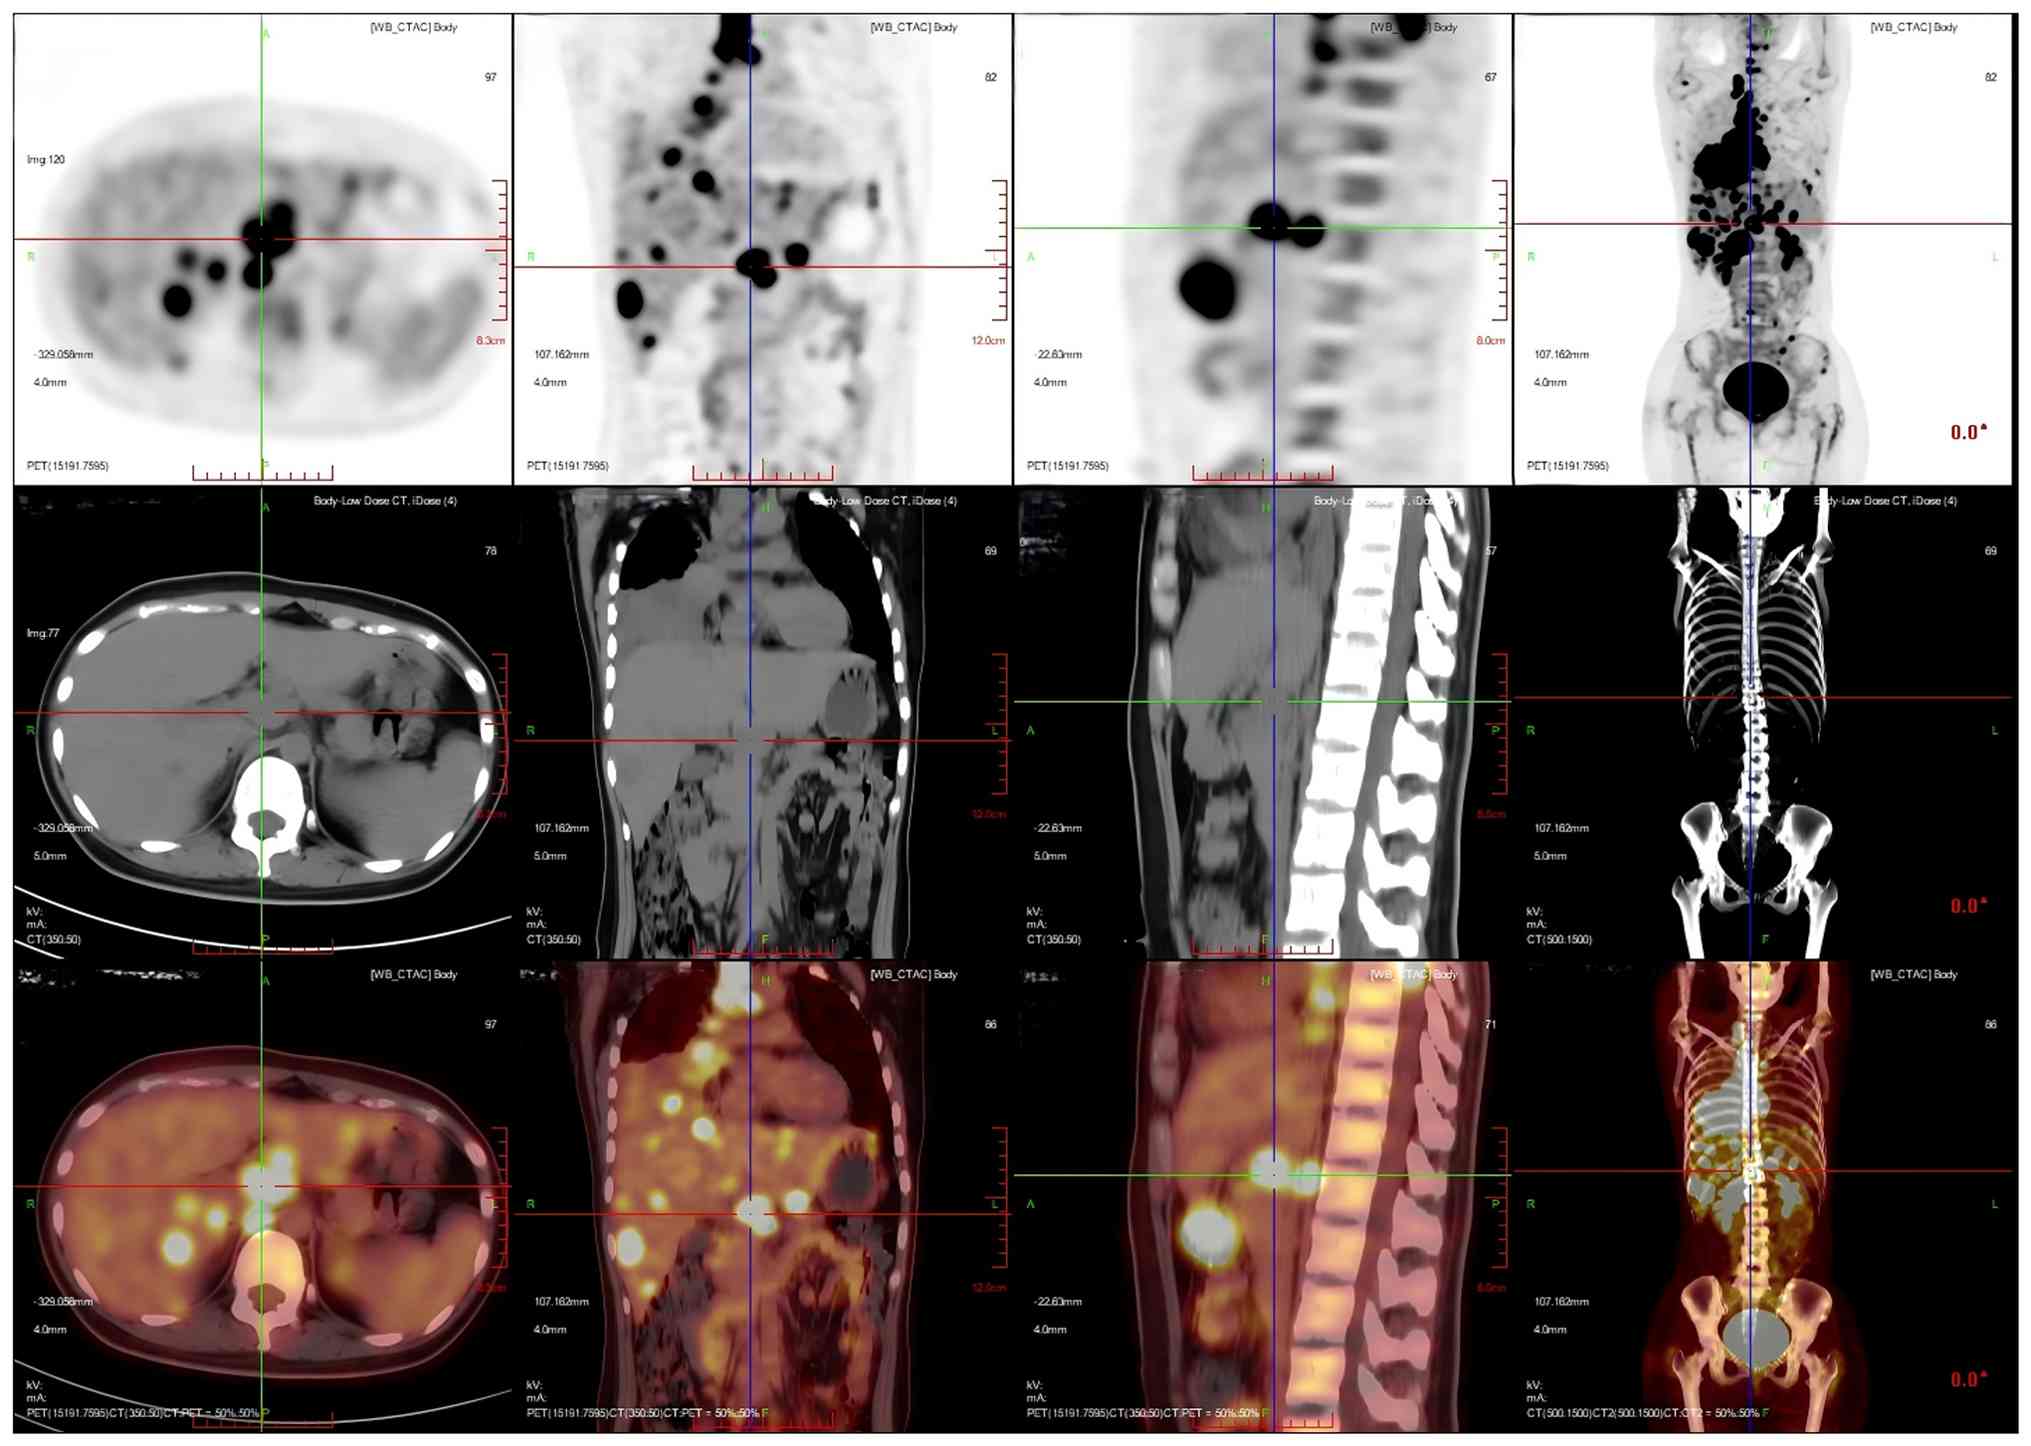

After 1 month, the patient developed numbness and discomfort below the waist, weakness of both lower limbs and limitations to lifting. To clarify the changes in the condition of the patient, positron emission tomography/CT (PET/CT) was performed. PET/CT images showed that an irregular mass-like hyperdense shadow was detected in the right lung hilar and the middle and lower lobes of the right lung; no normal lung tissue was seen, the lesion crossed the interlobular pleura and invaded the upper lobe of the right lung, and the corresponding area on PET showed a mass-like radiolucency focus with an maximum standardized uptake value (SUVmax) of 25.8 (Fig. 5). Multiple enlarged and swollen lymph nodes were detected in the mediastinum, bilateral pulmonary hilar region, bilateral diaphragmatic pedicle and right cardiogenic angle area, partially fused in the form of a mass. PET showed a mass of radiolucent foci in the corresponding areas, and the SUVmax of the hypermetabolic area under the bronchus was measured to be 21.4. Thickening of the right pleura was observed, an arcuate fluid density shadow was seen in the thoracic cavity and mild radiolucent uptake was visible in the area of pleural effusion on the right side of the chest cavity (Fig. 6). The liver was full, with diffuse low-density nodules and masses of varying sizes within it, and PET showed nodular and mass-like radioactivity uptake in the corresponding areas. The low-density mass in the S4 segment of the liver was measured to be ~5.0×4.4 cm in size, with an SUVmax of 20.0. Several enlarged lymph nodes were observed in the portal region of the liver, which had fused to form a mass. PET scans showed mass-like radioactivity uptake in the corresponding areas, with a SUVmax of 20.2 (Fig. 7). Multiple nodular and striated radiographic uptake of the right humeral head, multiple parts of the sternum, bilateral scapulae, cervical, thoracic and lumbar vertebral bodies, part of the accessory bones, the two flanks of the sacrum, multiple parts of the pelvic bone and the proximal segment of the left femur were noted. CT demonstrated an inhomogeneous increase in the density of the bone at the corresponding sites, discontinuity of the cortex in some of the neighboring bones, flattening of the seventh thoracic vertebral body, morphological disorders and an increase in the peripheral soft-tissue shadows. A high metabolic area was measured in the seventh thoracic vertebral body, with an SUVmax of 20.4 (Fig. 8).

Multiplanar 18F-FDG PET/CT imaging of

the patient's hypermetabolic mass lesion in the right lung. An

irregular mass-like hyperdense shadow was detected in the right

lung hilar and the middle and lower lobes of the right lung; no

normal lung tissue was seen, the lesion crossed the interlobular

pleura and invaded the upper lobe of the right lung, and the

corresponding area on positron emission tomography showed a

mass-like radiolucency focus with a SUVmax of 25.8.

Imaging modalities: PET (top row); CT (middle row); PET/CT fusion

imaging (bottom row). Imaging planes: Axial plane (first column)

showing cross-sectional views, with transaxial details of the right

pulmonary lesion. Coronal plane (second column): Frontal views

displaying craniocaudal extension of the lesion across right lung

lobes. Sagittal plane (third column): Lateral views illustrating

anteroposterior localization of the lesion relative to the hilum.

Volume-rendered CT (fourth column, middle row); a 3D reconstructed

thoracic CT scan depicting the bony thorax and spatial context of

the pulmonary lesion. CT, computed tomography; PET, positron

emission tomography.

Figure 5.

Multiplanar 18F-FDG PET/CT imaging of the patient's hypermetabolic mass lesion in the right lung. An irregular mass-like hyperdense shadow was detected in the right lung hilar and the middle and lower lobes of the right lung; no normal lung tissue was seen, the lesion crossed the interlobular pleura and invaded the upper lobe of the right lung, and the corresponding area on positron emission tomography showed a mass-like radiolucency focus with a SUVmax of 25.8. Imaging modalities: PET (top row); CT (middle row); PET/CT fusion imaging (bottom row). Imaging planes: Axial plane (first column) showing cross-sectional views, with transaxial details of the right pulmonary lesion. Coronal plane (second column): Frontal views displaying craniocaudal extension of the lesion across right lung lobes. Sagittal plane (third column): Lateral views illustrating anteroposterior localization of the lesion relative to the hilum. Volume-rendered CT (fourth column, middle row); a 3D reconstructed thoracic CT scan depicting the bony thorax and spatial context of the pulmonary lesion. CT, computed tomography; PET, positron emission tomography.